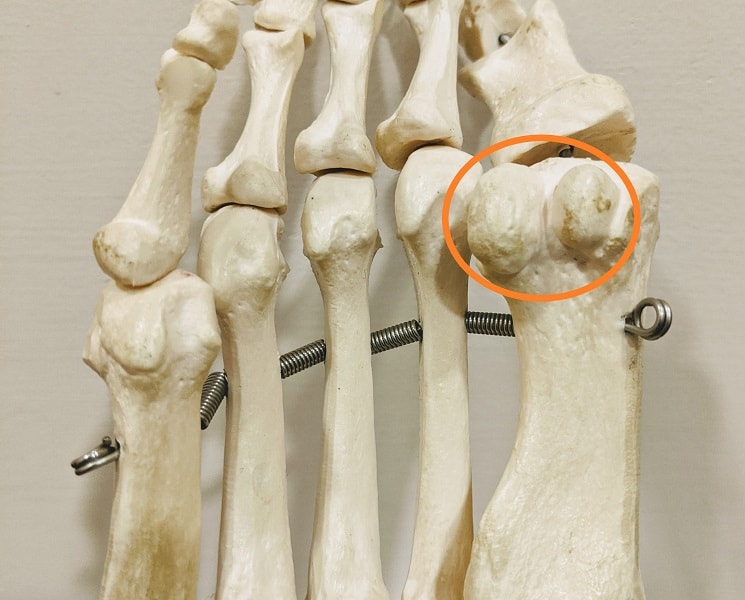

Перелом сесамовидной кости: Визуализация травмы и её лечение